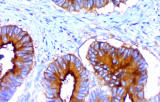

A imunohistoquímica (IHQ) com anticorpos primários CE/IVD é essencial para o diagnóstico e classificação precisos de malignidades ginecológicas e mamárias. Estes anticorpos permitem a deteção precisa de marcadores tumorais e proteínas celulares, apoiando o diagnóstico diferencial e guiando estratégias terapêuticas personalizadas.

Estudos recentes destacam o valor diagnóstico das proteínas do complexo SWI/SNF, particularmente ARID1B, na identificação de malignidades ginecológicas desdiferenciadas e indiferenciadas – tumores agressivos com mau prognóstico. A IHQ de ARID1B oferece elevada especificidade e está cada vez mais integrada em painéis diagnósticos para melhorar a precisão. Painéis com marcadores adicionais também apoiam a diferenciação de sarcomas uterinos, aumentando a exatidão diagnóstica. Evidência emergente sugere que ARID1B pode representar um alvo terapêutico potencial no carcinoma ovárico de células claras, embora as aplicações clínicas permaneçam em fase investigacional.

Anticorpos primários contra recetor de estrogénio (ER), recetor de progesterona (PR), HER2 e Ki-67 continuam a ser a pedra angular da classificação e decisões terapêuticas no cancro da mama. Estes anticorpos estão validados clinicamente e marcados CE/IVD para garantir deteção fiável e reproduzível de biomarcadores – crucial para orientar terapia hormonal e estratégias de tratamento direcionado.